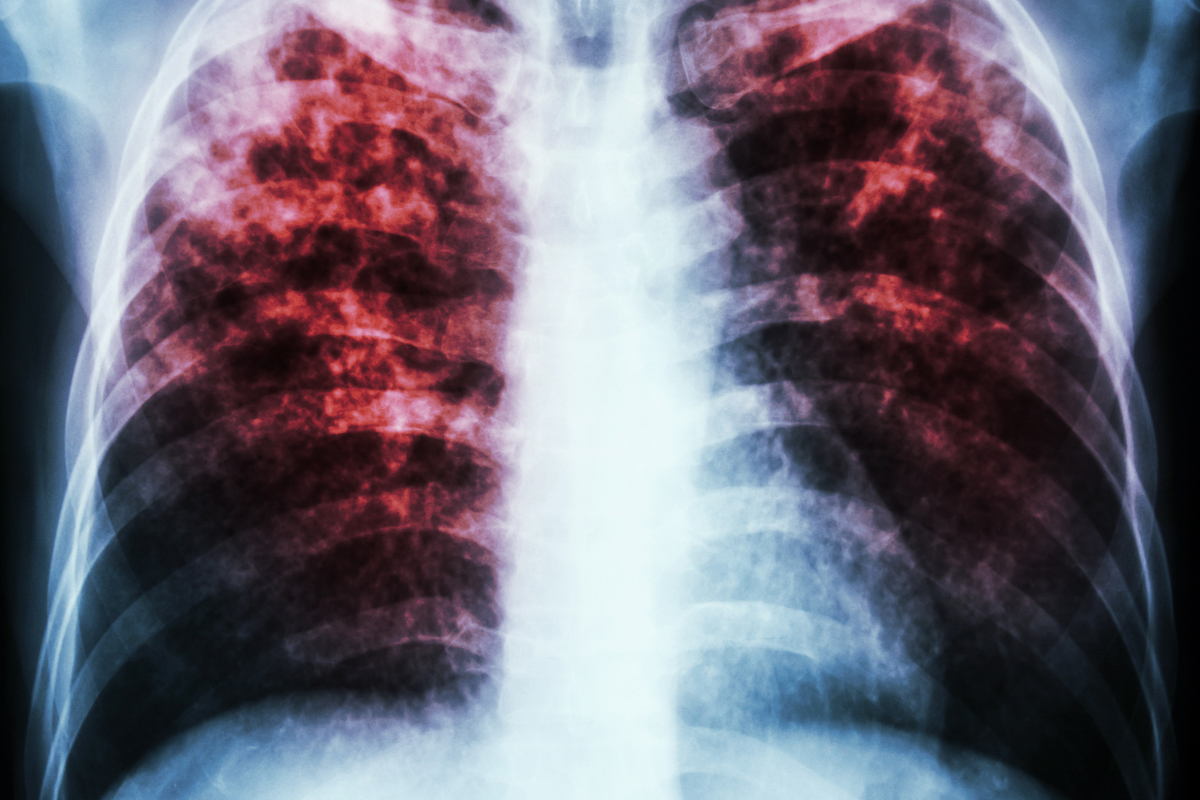

How COPD Affects the Respiratory System

Airflow Limitation and Breathing Difficulties

COPD is known for causing airflow limitation, which makes breathing difficult. This happens because COPD damages the airways and lung tissue. People with COPD often find it hard to breathe, even when doing simple things.

The airflow problem in COPD doesn’t get better and gets worse over time. This can make symptoms worse and lower quality of life. The main reasons for this problem are:

- Inflammation and narrowing of the airways

- Damage to the alveoli, reducing gas exchange efficiency

- Increased mucus production, further obstructing airflow

Long-term Effects on Lung Function

COPD has big effects on lung function over time. It makes it harder for the lungs to get oxygen and get rid of carbon dioxide. Doctors use spirometry tests to see how well lungs are working by measuring air exhaled.